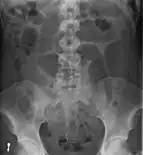

Plain X ray of a cecal volvulus